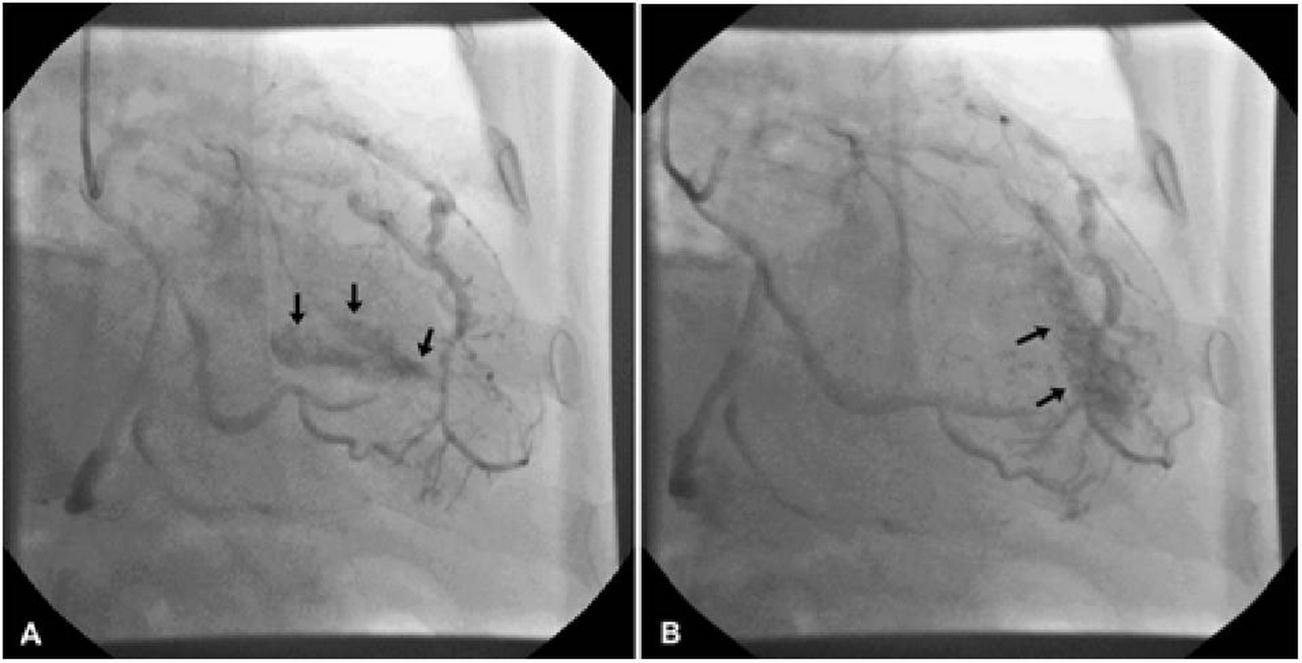

He was asymptomatic, in good general conditions, blood pressure 120/80 mmHg, no murmurs. The electrocardiogram showed sinus bradycardia (55 bpm) and left ventricular hypertrophy signs (deep and symmetric negative T waves in DI, aVL, V2 till V6). Echocardiogram (VIVID 7, 2-4 MHz probe) showed non classical apical hypertrophic cardiomyopathy (Figure 2), localized at anterior, lateral and posterior apex (septum was preserved), with no obliteration of apical cavity. By mean of color-Doppler evaluation, we observed multiple and thin color flows from LAD draining into apical region. Pulse-wave Doppler temporization was exclusively diastolic (Figure 3). Stress echocardiography with accelerate dipyridamole resulted negative for inducible ischemia and no variation in fistula flow was detectable. Inguinal hernia intervention was safely performed and the patient was advised to undergo periodical cardiologic controls.

Figure 2.Echocardiogram image of non classical apical hypertrophic cardiomyopathy of the patient.

Echocardiogram image of non classical apical hypertrophic cardiomyopathy of the patient.